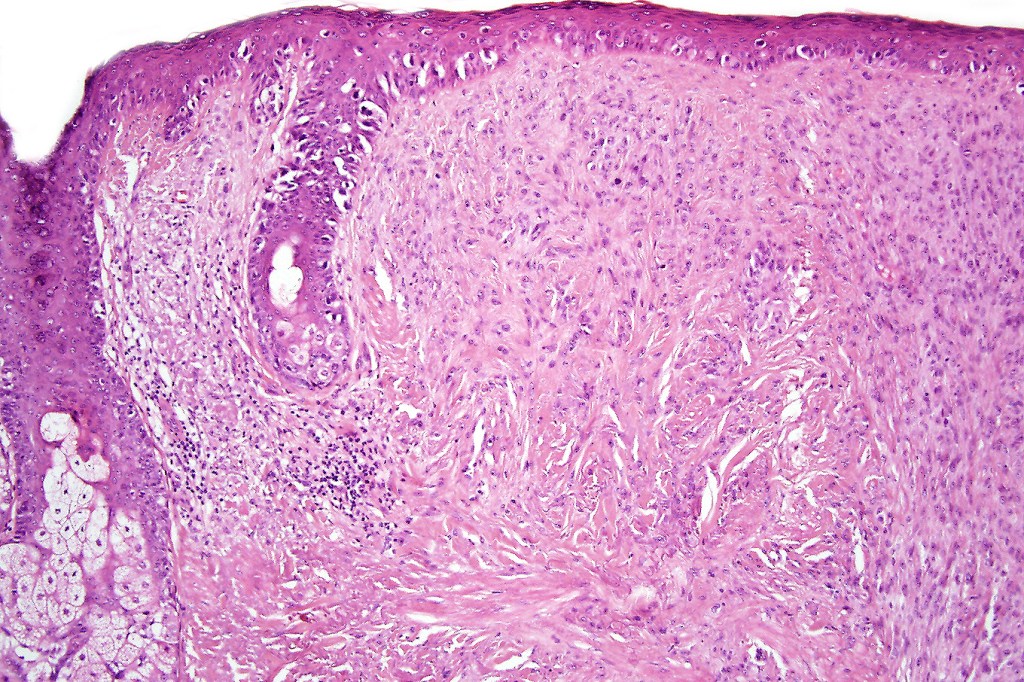

•Invasive tumor (lentigo maligna melanoma) typically characterized by a spindle cell population

•Invasion can be subtle and may require immunohistochemistry

•Desmoplastic and neurotropic melanoma in a significant number of cases